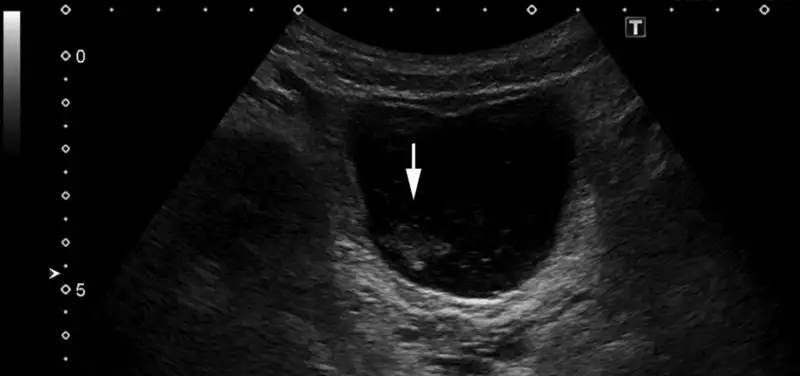

Featured Image: Large amount of echogenic debris within the urinary bladder compatible with history of urinary tract infection.